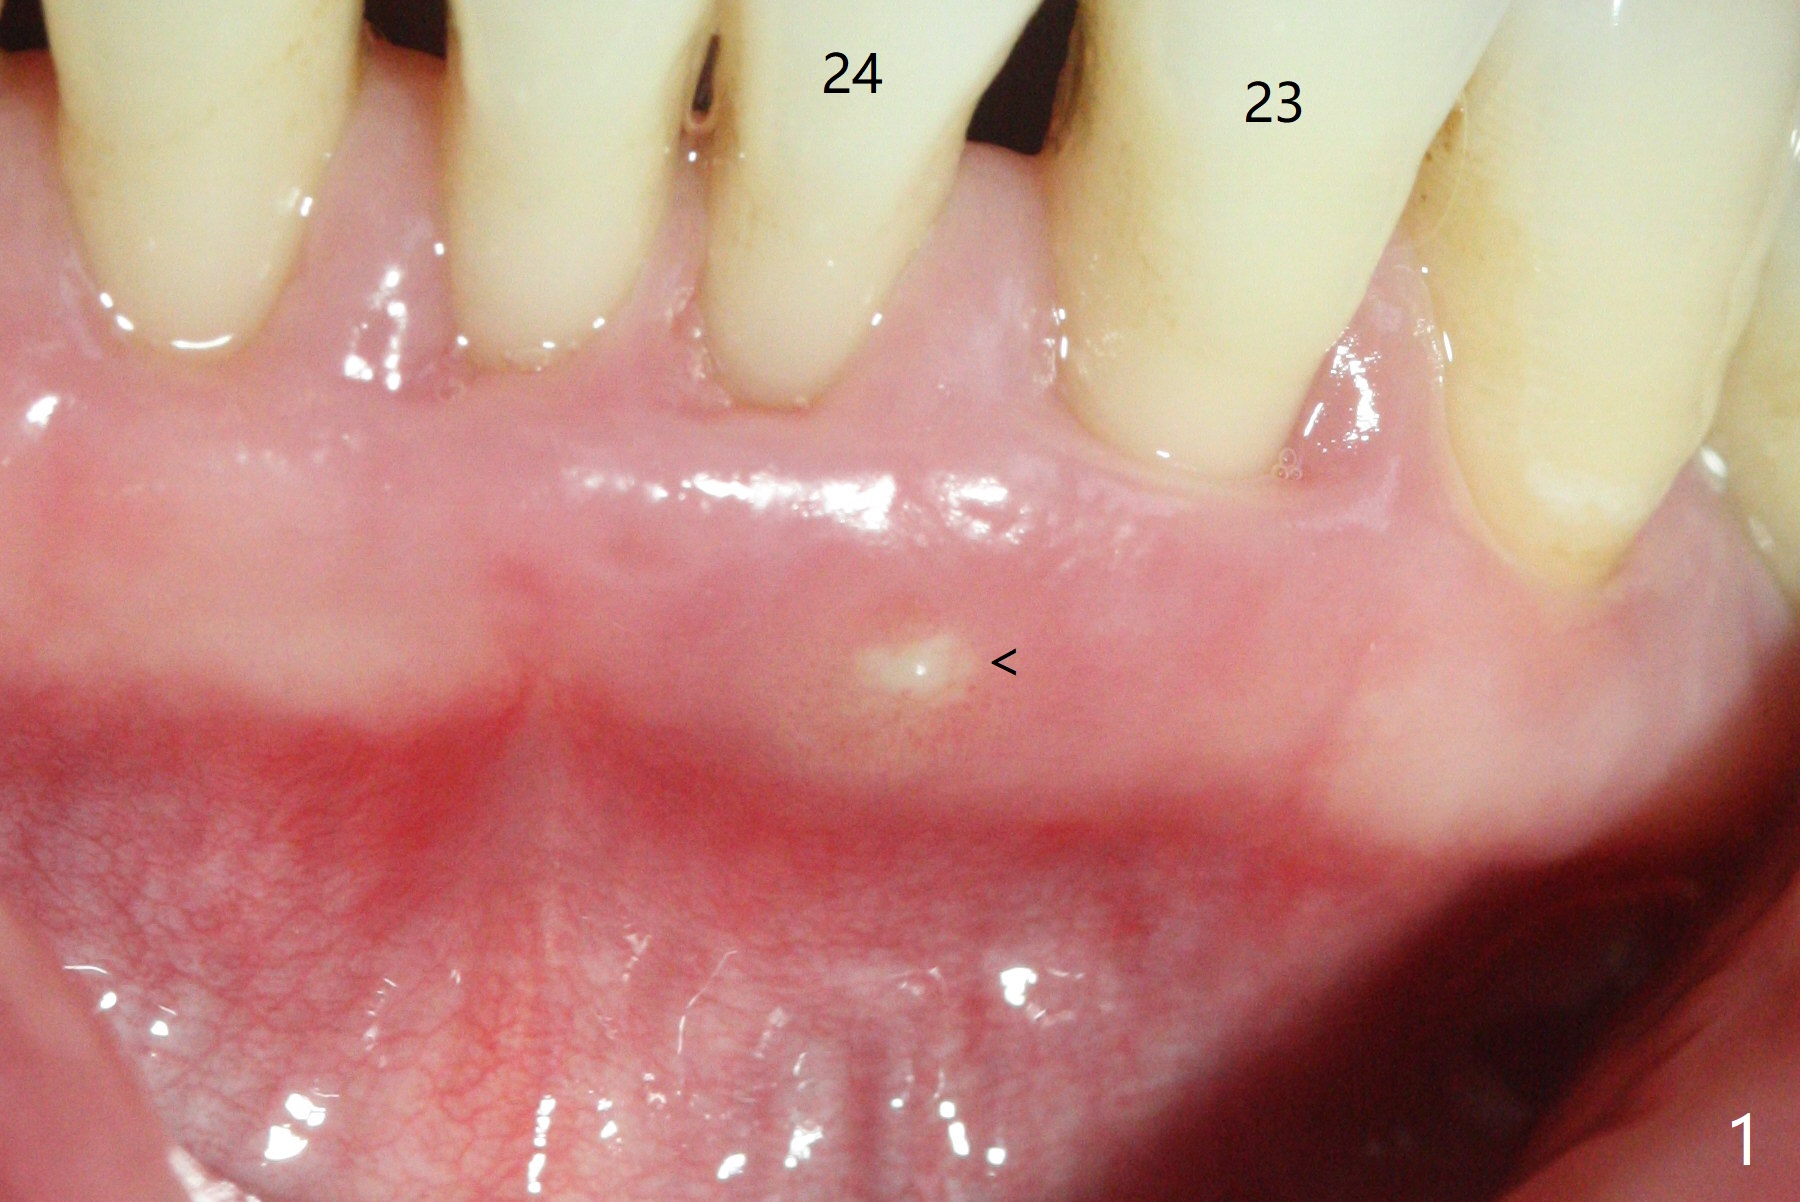

A 45-year-old woman returns for perio maintenance with erythematous and edematous papilla between #23 and 24. Two days later the infection subsides with sinus track (Fig.1 <). With infiltration anesthesia, Waterlase is used for outer and inner (steps 1,3) pocket de-epithelization (and retratction), and sulcular debridement/degranulation (step 5, Fig.3). Gingivectomy (step 2) is omitted because of severe existing gingival recession. Scaling and root planing is not conducted since step 3 seems to be able to remove fine subgingival calculus (Fig.2 <). But it appears not sufficient (Fig.4). Bone decortication should be implemented in future cases (step 6). Mepivacaine is administered in block fashion immediately postop for pain control. The patient is doing fine postop.